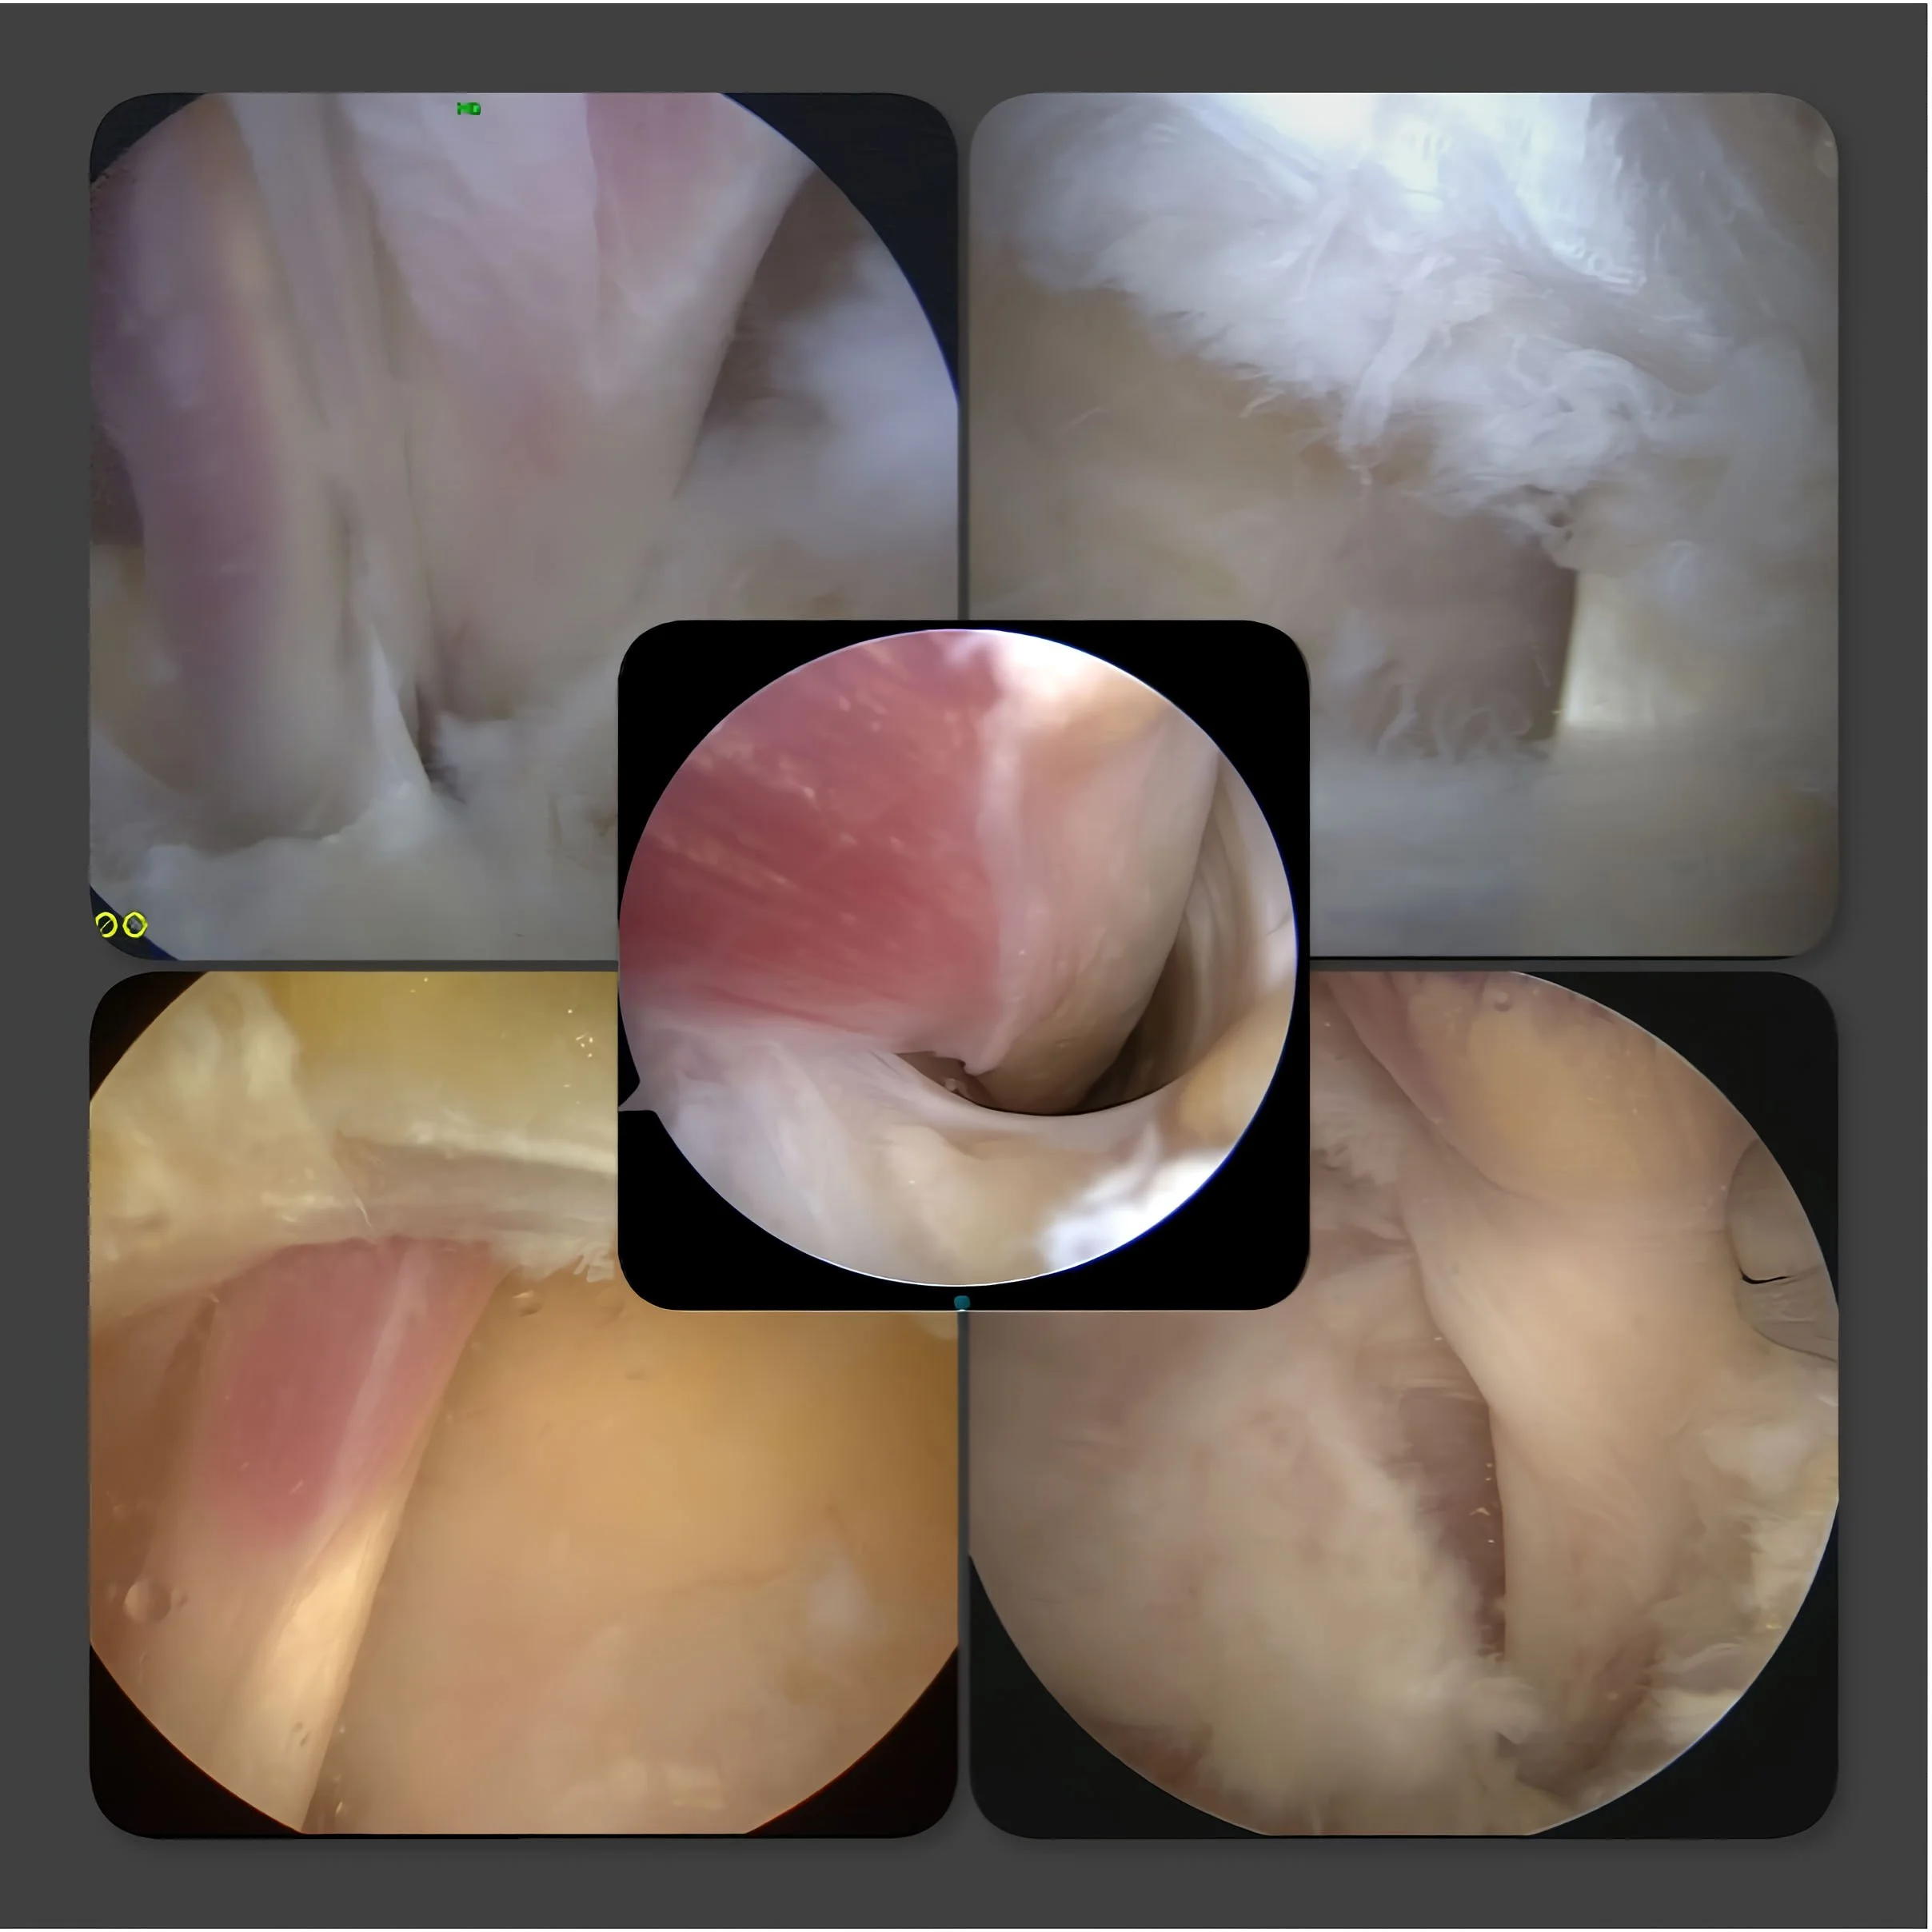

Via de kijkoperatie techniek kunnen verschillende operaties uitgevoerd worden, zoals:

• Verwijderen van een los botfragment aan de achterzijde van de enkel.

• Bijslijpen van het uitsteeksel van het sprongbeen, hierdoor kan de beweeglijkheid van het enkelgewricht verbeteren.

• Verwijderen van littekenweefsel of verkalkingen.

• Losmaken van de grote lange teenbuiger.

Natuurlijk kan zowel het onderste als het bovenste spronggewricht worden beoordeeld. Om de operatie te kunnen uitvoeren ligt u op uw buik en is een algemene verdoving of een ruggenprik nodig.

De sneetjes van ongeveer 5 mm worden net naast de achillespees gemaakt. Via het ene sneetje wordt de camera naar binnengebracht en via het andere sneetje de instrumenten. Nu kan via een scherm de operatie worden uitgevoerd. Vaak wordt gebruik gemaakt van verschillende instrumenten.

Bij de operatie aan de achterzijde van de enkel moet er altijd eerst weefsel worden verwijderd, omdat de operatie niet direct in het gewricht begint. Het meeste wordt gedaan aan de achterzijde van het bovenste spronggewricht. Natuurlijk wordt ook het enkelgewricht bekeken en zo nodig schoongemaakt. Omdat er meer weefsel verwijderd zal moeten worden in vergelijking met bijvoorbeeld een kijkoperatie van de voorzijde van de enkel of van de knie, is de enkel na de operatie nog lang dik. Het kan prettig zijn om compressie kousen te gebruiken.